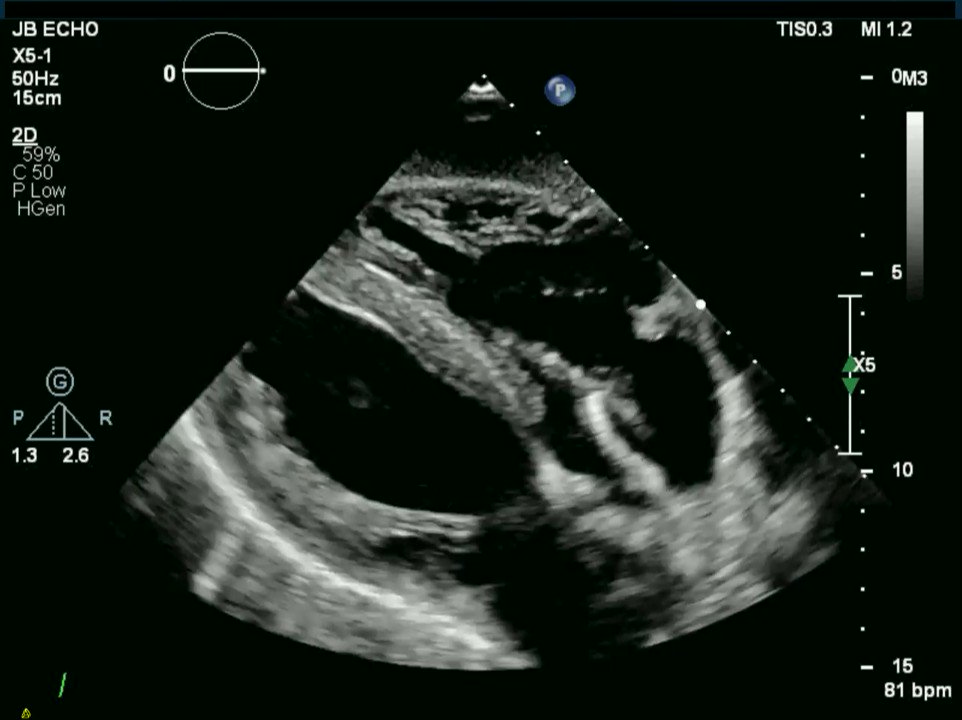

Figure 2 from A case report of Enterobacter cloacae endocarditis in a Cotton Fever Endocarditis infective endocarditis is a potentially lethal disease that has undergone major changes in both host and pathogen. the management of infective endocarditis (ie) includes prompt diagnosis, treatment with antimicrobial therapy, and. although cotton fever is a diagnosis of exclusion, an increased awareness of this condition would likely. Cotton fever is an illness that happens to some people. Cotton Fever Endocarditis.